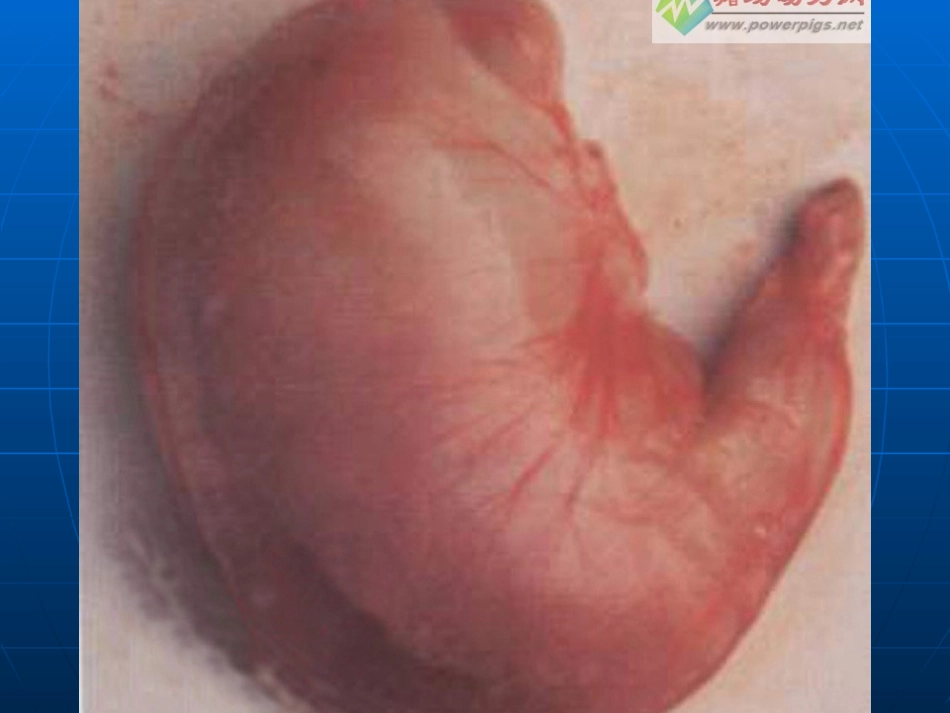

胃炎健康知识讲座Gastritis发病率成人几乎100%有症状达30~70%定义:一、概述:各种病因慢性胃炎急性胃炎胃粘膜的炎症不同原因所致胃黏膜急性和慢性炎症不同原因所致胃黏膜急性和慢性炎症胃炎胃炎急性胃炎急性胃炎慢性胃炎慢性胃炎非萎缩性胃炎非萎缩性胃炎(浅表性胃炎)(浅表性胃炎)萎缩性胃炎萎缩性胃炎((AA型,型,BB型型))特殊类型胃炎特殊类型胃炎化学性胃炎放射性胃炎淋巴细胞性胃炎肉芽肿性胃炎嗜酸细胞性胃炎其他分类分类:胃镜分类胃镜分类慢性萎缩性胃炎慢性非萎缩性胃炎国内分类急性胃炎定义定义急性胃炎系由不同病因引起的急性胃炎系由不同病因引起的胃粘膜胃粘膜急性炎症。急性炎症。病变严重者可累及粘膜下层与肌层,甚至深达病变严重者可累及粘膜下层与肌层,甚至深达浆膜层。浆膜层。临床上按病因及病理变化的不同,分为急性单临床上按病因及病理变化的不同,分为急性单纯性胃炎、急性糜烂性胃炎、急性腐蚀性胃炎、纯性胃炎、急性糜烂性胃炎、急性腐蚀性胃炎、急性化脓性胃炎。急性化脓性胃炎。其中临床上以急性单纯性胃炎最为常见,而由其中临床上以急性单纯性胃炎最为常见,而由于抗生素广泛应用,急性化脓性胃炎已罕见。于抗生素广泛应用,急性化脓性胃炎已罕见。导致发病的因素很多导致发病的因素很多::有有化学化学或或物理物理的刺激,的刺激,也有也有细菌或其毒素细菌或其毒素引起。引起。化学刺激化学刺激主要来自烈酒、浓茶、咖啡、香料及主要来自烈酒、浓茶、咖啡、香料及药物药物((如水杨酸盐制剂、消炎痛、保泰松、糖如水杨酸盐制剂、消炎痛、保泰松、糖皮质激素等皮质激素等)),其中急性腐蚀性胃炎多是由吞,其中急性腐蚀性胃炎多是由吞服强酸、强碱及其他腐蚀剂所致。服强酸、强碱及其他腐蚀剂所致。物理刺激物理刺激如过热、过冷、过于粗糙的食物及如过热、过冷、过于粗糙的食物及XX线照射,均会损伤胃粘膜,引起炎症性改变。线照射,均会损伤胃粘膜,引起炎症性改变。病因病因病因病因生物因素生物因素细菌及其毒素细菌及其毒素。常见致病菌为沙门菌、嗜盐菌、。常见致病菌为沙门菌、嗜盐菌、致病性大肠杆菌等,常见毒素为金黄色葡萄球菌或毒素杆致病性大肠杆菌等,常见毒素为金黄色葡萄球菌或毒素杆菌毒素,尤其是前者较为常见。菌毒素,尤其是前者较为常见。进食污染细菌或毒素的食进食污染细菌或毒素的食物数小时后即可发生胃炎或同时合并肠炎此即急性胃肠炎。物数小时后即可发生胃炎或同时合并肠炎此即急性胃肠炎。葡萄球菌及其毒素摄入后合并肠炎此即葡萄球菌及其毒素摄入后合并肠炎此即急性胃肠炎急性胃肠炎。。精神、神经因素。精神、神经因素。精神、神经功能失调,各种急重症的精神、神经功能失调,各种急重症的危急状态,以及机体的变态危急状态,以及机体的变态((过敏过敏))反应均可引起胃粘膜反应均可引起胃粘膜的急性炎症损害。的急性炎症损害。胃内异物或胃石、胃区放射治疗均可作为外源性刺激,导胃内异物或胃石、胃区放射治疗均可作为外源性刺激,导致本病。情绪波动、应激状态及体内各种因素引起的变态致本病。情绪波动、应激状态及体内各种因素引起的变态反应可作为反应可作为内源性刺激内源性刺激而致病。而致病。精神刺激病因和发病机理急性应急胃粘膜缺血、缺氧粘液、碳酸氢盐分泌减少前列腺素合成不足粘膜屏障破坏糜烂、出血临床表现临床表现家庭生活中一般在暴饮暴食或食用了污染食物、家庭生活中一般在暴饮暴食或食用了污染食物、服对胃有刺激的药后数小时至服对胃有刺激的药后数小时至2424小时发病。主要为:小时发病。主要为:1.1.上腹痛正中偏左或脐周压痛,呈阵发性加重或持续上腹痛正中偏左或脐周压痛,呈阵发性加重或持续性钝痛,伴腹部饱胀、不适。少数病人出现剧痛。性钝痛,伴腹部饱胀、不适。少数病人出现剧痛。2.2.恶心、呕吐呕吐物为未消化的食物,吐后感觉舒服,恶心、呕吐呕吐物为未消化的食物,吐后感觉舒服,也有的病人直至呕吐出黄色胆汁或胃酸。也有的病人直至呕吐出黄色胆汁或胃酸。3.3.腹泻伴发肠炎者出现腹泻,随胃部症状好转而停止,腹泻伴发肠炎者出现腹泻,随胃部症...